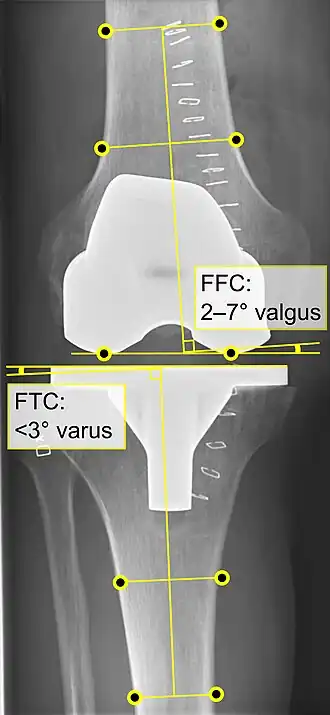

Knee replacement is routinely evaluated by X-ray, including the following measures:

- FFC: frontal femoral component angle. It is typically regarded as optimal when being 2–7° in valgus.[63]

- FTC: frontal tibial component angle, which is regarded as optimal when being at a right angle. A varus position of more than 3° has generally been found to increase the failure rate of the prosthesis.[63] -